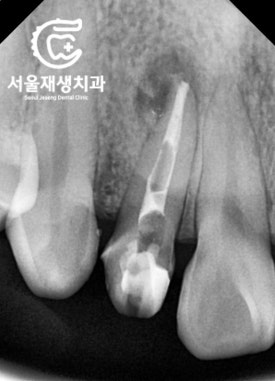

반복되는 청소, 소독

뿌리 내에 있던

기존 재료를 모두 제거하고

그 자리에 소독연고를

도포해둔 상태입니다.

엑스레이상 흰 색으로 보입니다.

소독하는 과정을 반복합니다.

이제는 4주에 한 번정도 오셔서

간단히 소독하고 약을 교체하지요.

통증은 거의 없습니다.